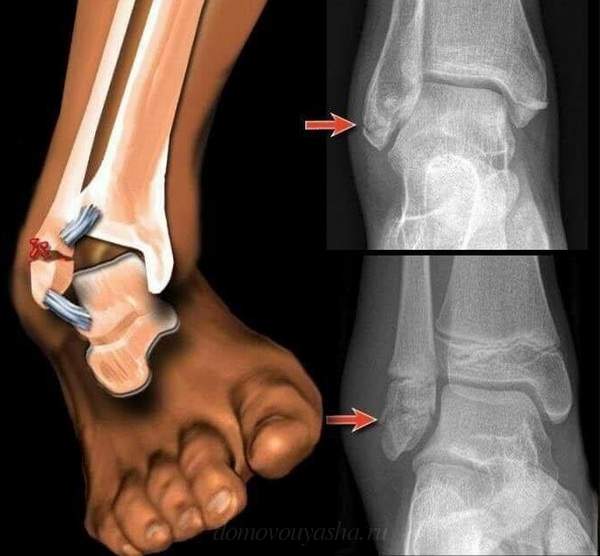

На голеностопе расположено несколько групп связок, представленных на рисунке ниже:

Как выглядит разрыв связок голеностопа, фото

В первые часы после разрыва трудно поставить диагноз по внешним признакам. Однако на вторые сутки уже можно отчетливо заметить признаки данной травмы. Понять, что у пострадавшего порваны связки, можно по синеве в месте травмы, обширному отеку, а иногда и по деформации голеностопа, который выкручивается в более удобное положение.

Чтобы знать, как визуально выглядит разрыв связок голеностопа, посмотрите фото: